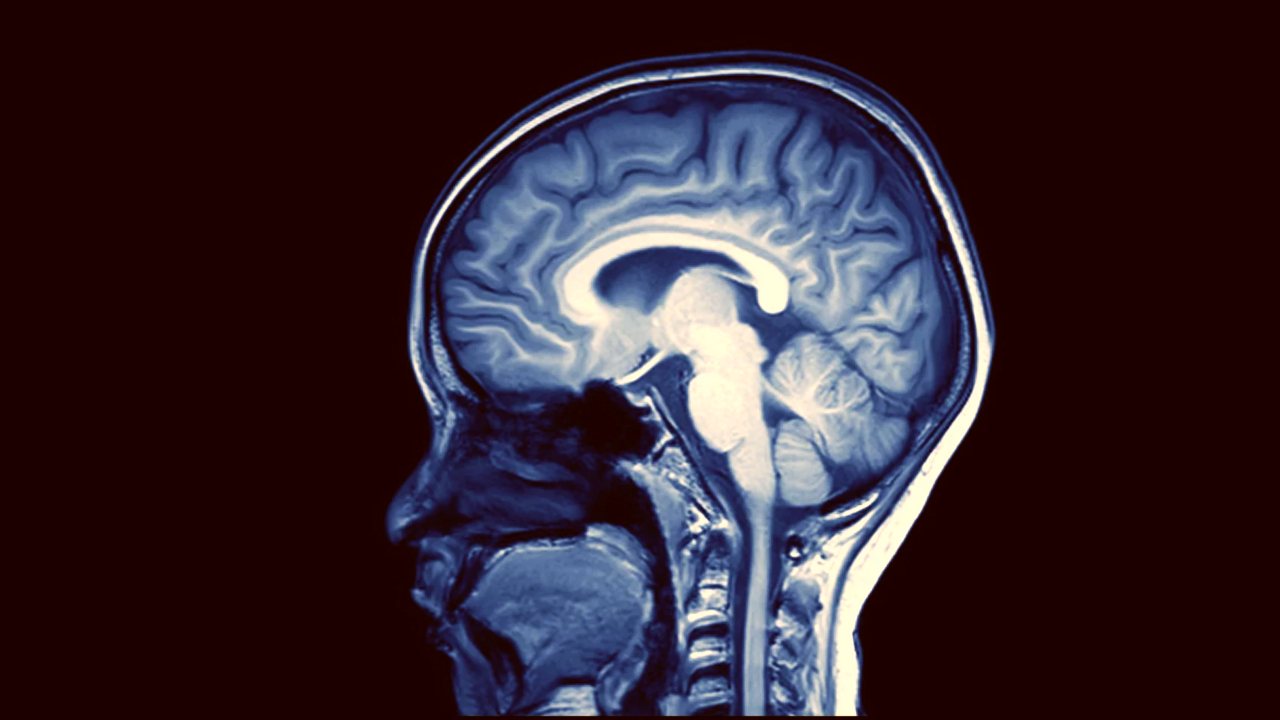

Being forgetful about a few things is okay. You may sometime forget to switch off the fans or find it very difficult to remember the name of your distant cousin. Being forgetful comes naturally with aging as well. However, conditions such as dementia may affect brain function and lead to severe memory loss. So when does someone actually know that their dear one may be suffering from Alzheimer’s or any other form of dementia? As per the US National Institute of Ageing, patients suffering from Alzheimer’s along with memory loss experience various other problems. They may forget their address and wander clueless for a very long time. They may find it very difficult to deal with numbers and pay their bills. Such people may exhibit behavioural changes and may have difficulty in carrying out their daily activities. [caption id=“attachment_7375441” align=“alignnone” width=“1280”] Brain scan showing signs of dementia. Image: Alzheimers.net[/caption] In severe cases, people may forget usual activities such as bathing and even responding to normal communication. Depending on the degree of symptoms, dementia can be one of three stages. Mild (First stage) dementia In this stage a person may be able to carry out normal activities such as driving, working, taking part in social activities, etc. However, they may experience memory elapses where they find it difficult to remember things they have just read, names of people they recently met and even forget some most commonly used words. The family and friends may begin to notice symptoms at this stage. Moderate (Second stage) dementia The second stage is the longest and may prevail for many years. During this stage, the patients may find it difficult to deal with numbers and forget even the most memorable days of their lives. They may be unable to recall the school and college they graduated from or the year they got married etc. Patients at this stage may have an altered sleep cycle. They may also be unable to decide what clothes they should wear as per the current season. Personality and behavioural changes become very prominent during this stage. Patients require a lot of attention and care to cope up with this condition. Late (Third stage) dementia In this stage, a person becomes completely unaware of the surroundings and doesn’t know how to respond or communicate. They may forget how to walk, sit or even swallow. During this stage, the patients require 24*7 assistance and care. [caption id=“attachment_7375481” align=“alignnone” width=“1280”]

To arrive at a diagnosis, the doctors may start by looking at the medical and family history of the patient. The patient’s mental functions are assessed in detailed way by standard medical scoring systems such as Mini-Mental State Examination (MMSE). The doctor may order imaging tests such as MRI and CT scan of the brain to rule out other causes of mental dysfunction, such as a tumor or an infection before Alzheimer’s can be diagnosed as it is a diagnosis of exclusion. Till now, there is no cure for Alzheimer’s; however, medications are available to help delay the progression of the disease and even control its symptoms. However, caring for Alzheimer’s patients is a big responsibility as people suffering from this condition require extensive medical care and support. Therefore, it is important for patients and caregivers to discuss all aspects of care with the treating team and prepare one.